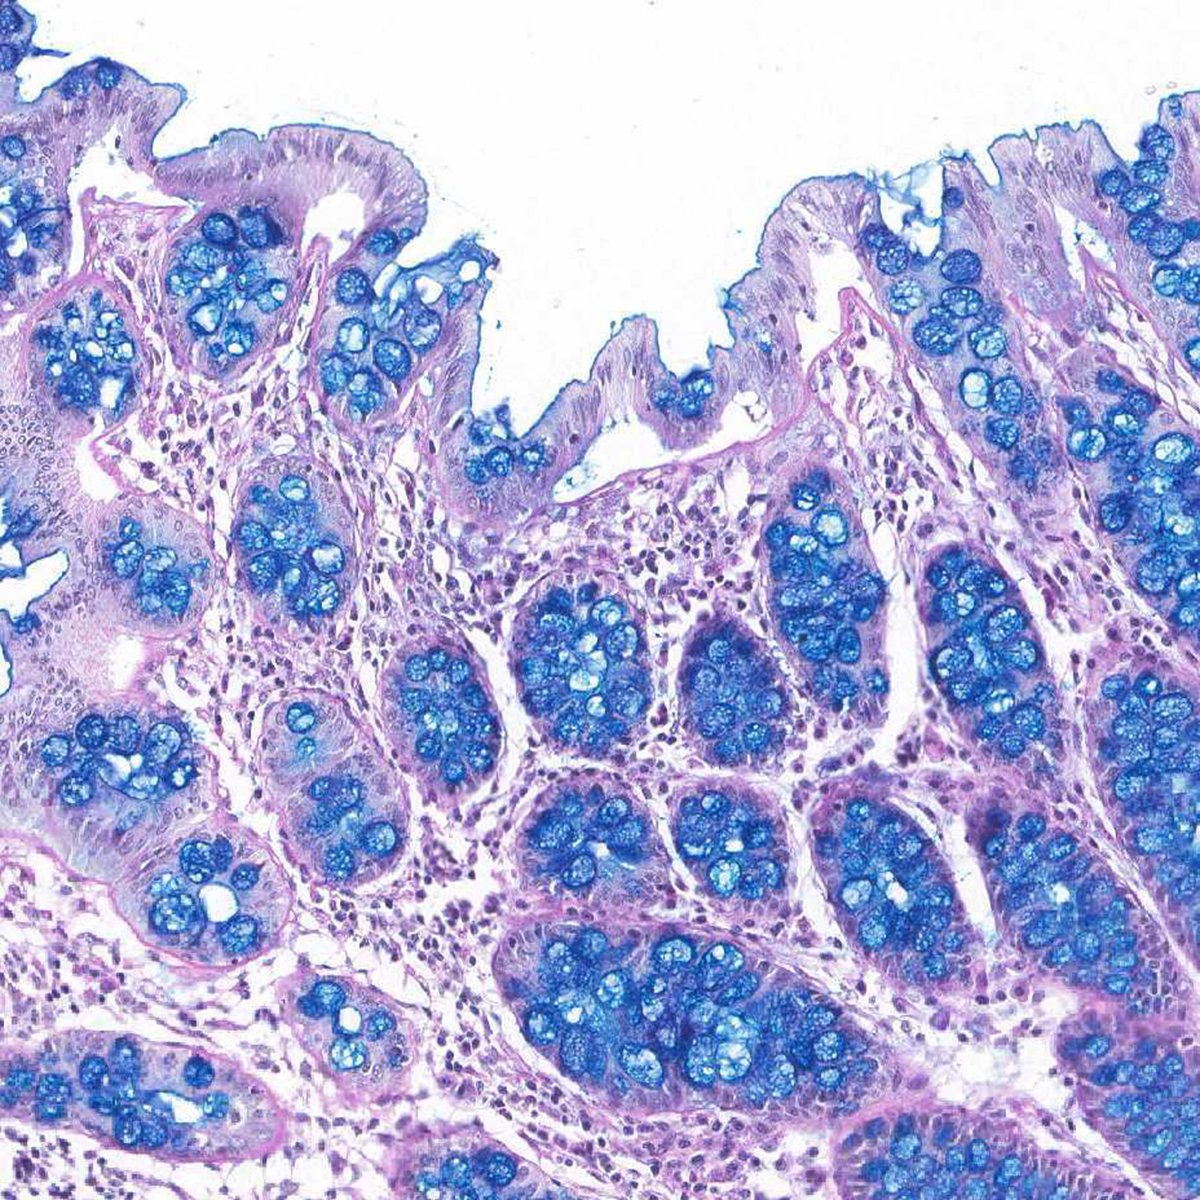

Resultados Esperados com o Corante Alcian Blue

A leitura das lâminas processadas com o Histokit Alcian Blue pH 2,5 segue padrão cromogênico definido, facilitando a interpretação objetiva pelo patologista e a comparação entre casos. O protocolo de coloração alcian blue entrega:

- ✓ Mucopolissacarídeos ácidos — azul turquesa (positivo)

- ✓ Núcleos celulares — roxo (contrastante pela Hematoxilina de Harris)

A nitidez do contraste entre estruturas positivas e negativas é mantida mesmo em cortes com alta densidade celular, favorecendo a análise quantitativa e a documentação fotomicrográfica.